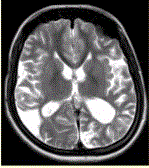

问题 女性,22岁。癫痫发作及智力异常。MRI显示见下图。 关于该病,最可能的原因是

选项 A.海绵状血管瘤 B.发育性静脉畸形 C.AVM D.毛细血管扩张症 E.动脉瘤 F.硬脑膜动静脉瘘 G.moyamoya

答案 CG